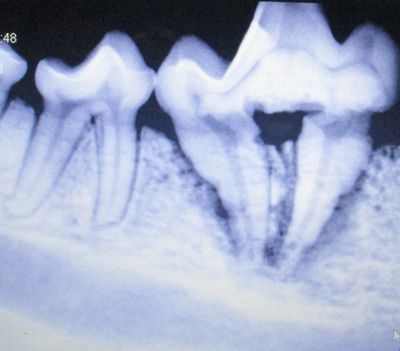

A complete oral exam and digital dental radiographs are taken to identify any problems beneath the gum-line. (This is similar to the x-rays you might receive from your own dentist.) Common painful problems that could be identified with radiographs are broken teeth and roots, periodontal disease, dead teeth, abscesses or infected teeth.